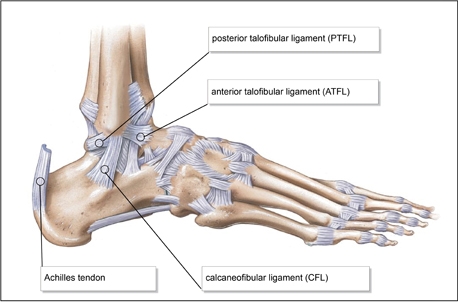

Anatomia dos Ligamentos do Tornozelo

A estabilidade do tornozelo é garantida por três grupos principais de ligamentos: ligamento talofibular anterior (LTA), ligamento calcaneofibular (LCF) e ligamento talofibular posterior (LTP). O LTA é o mais comumente lesado nas entorses de tornozelo, principalmente em entorses por inversão. Esses ligamentos estabilizam a articulação tibiofibular e mantêm o alinhamento adequado entre o talus e o calcâneo, limitando movimentos exagerados que podem levar à instabilidade.

Ligamentos Afetados Comumente:

- Ligamento Talofibular Anterior (LTA): mais suscetível a lesões devido à posição e ao movimento de inversão.

- Ligamento Calcaneofibular (LCF): frequentemente lesionado em entorses mais graves que envolvem uma rotação do tornozelo.

- Ligamento Talofibular Posterior (LTP): menos frequentemente lesionado, mas também importante para estabilidade.